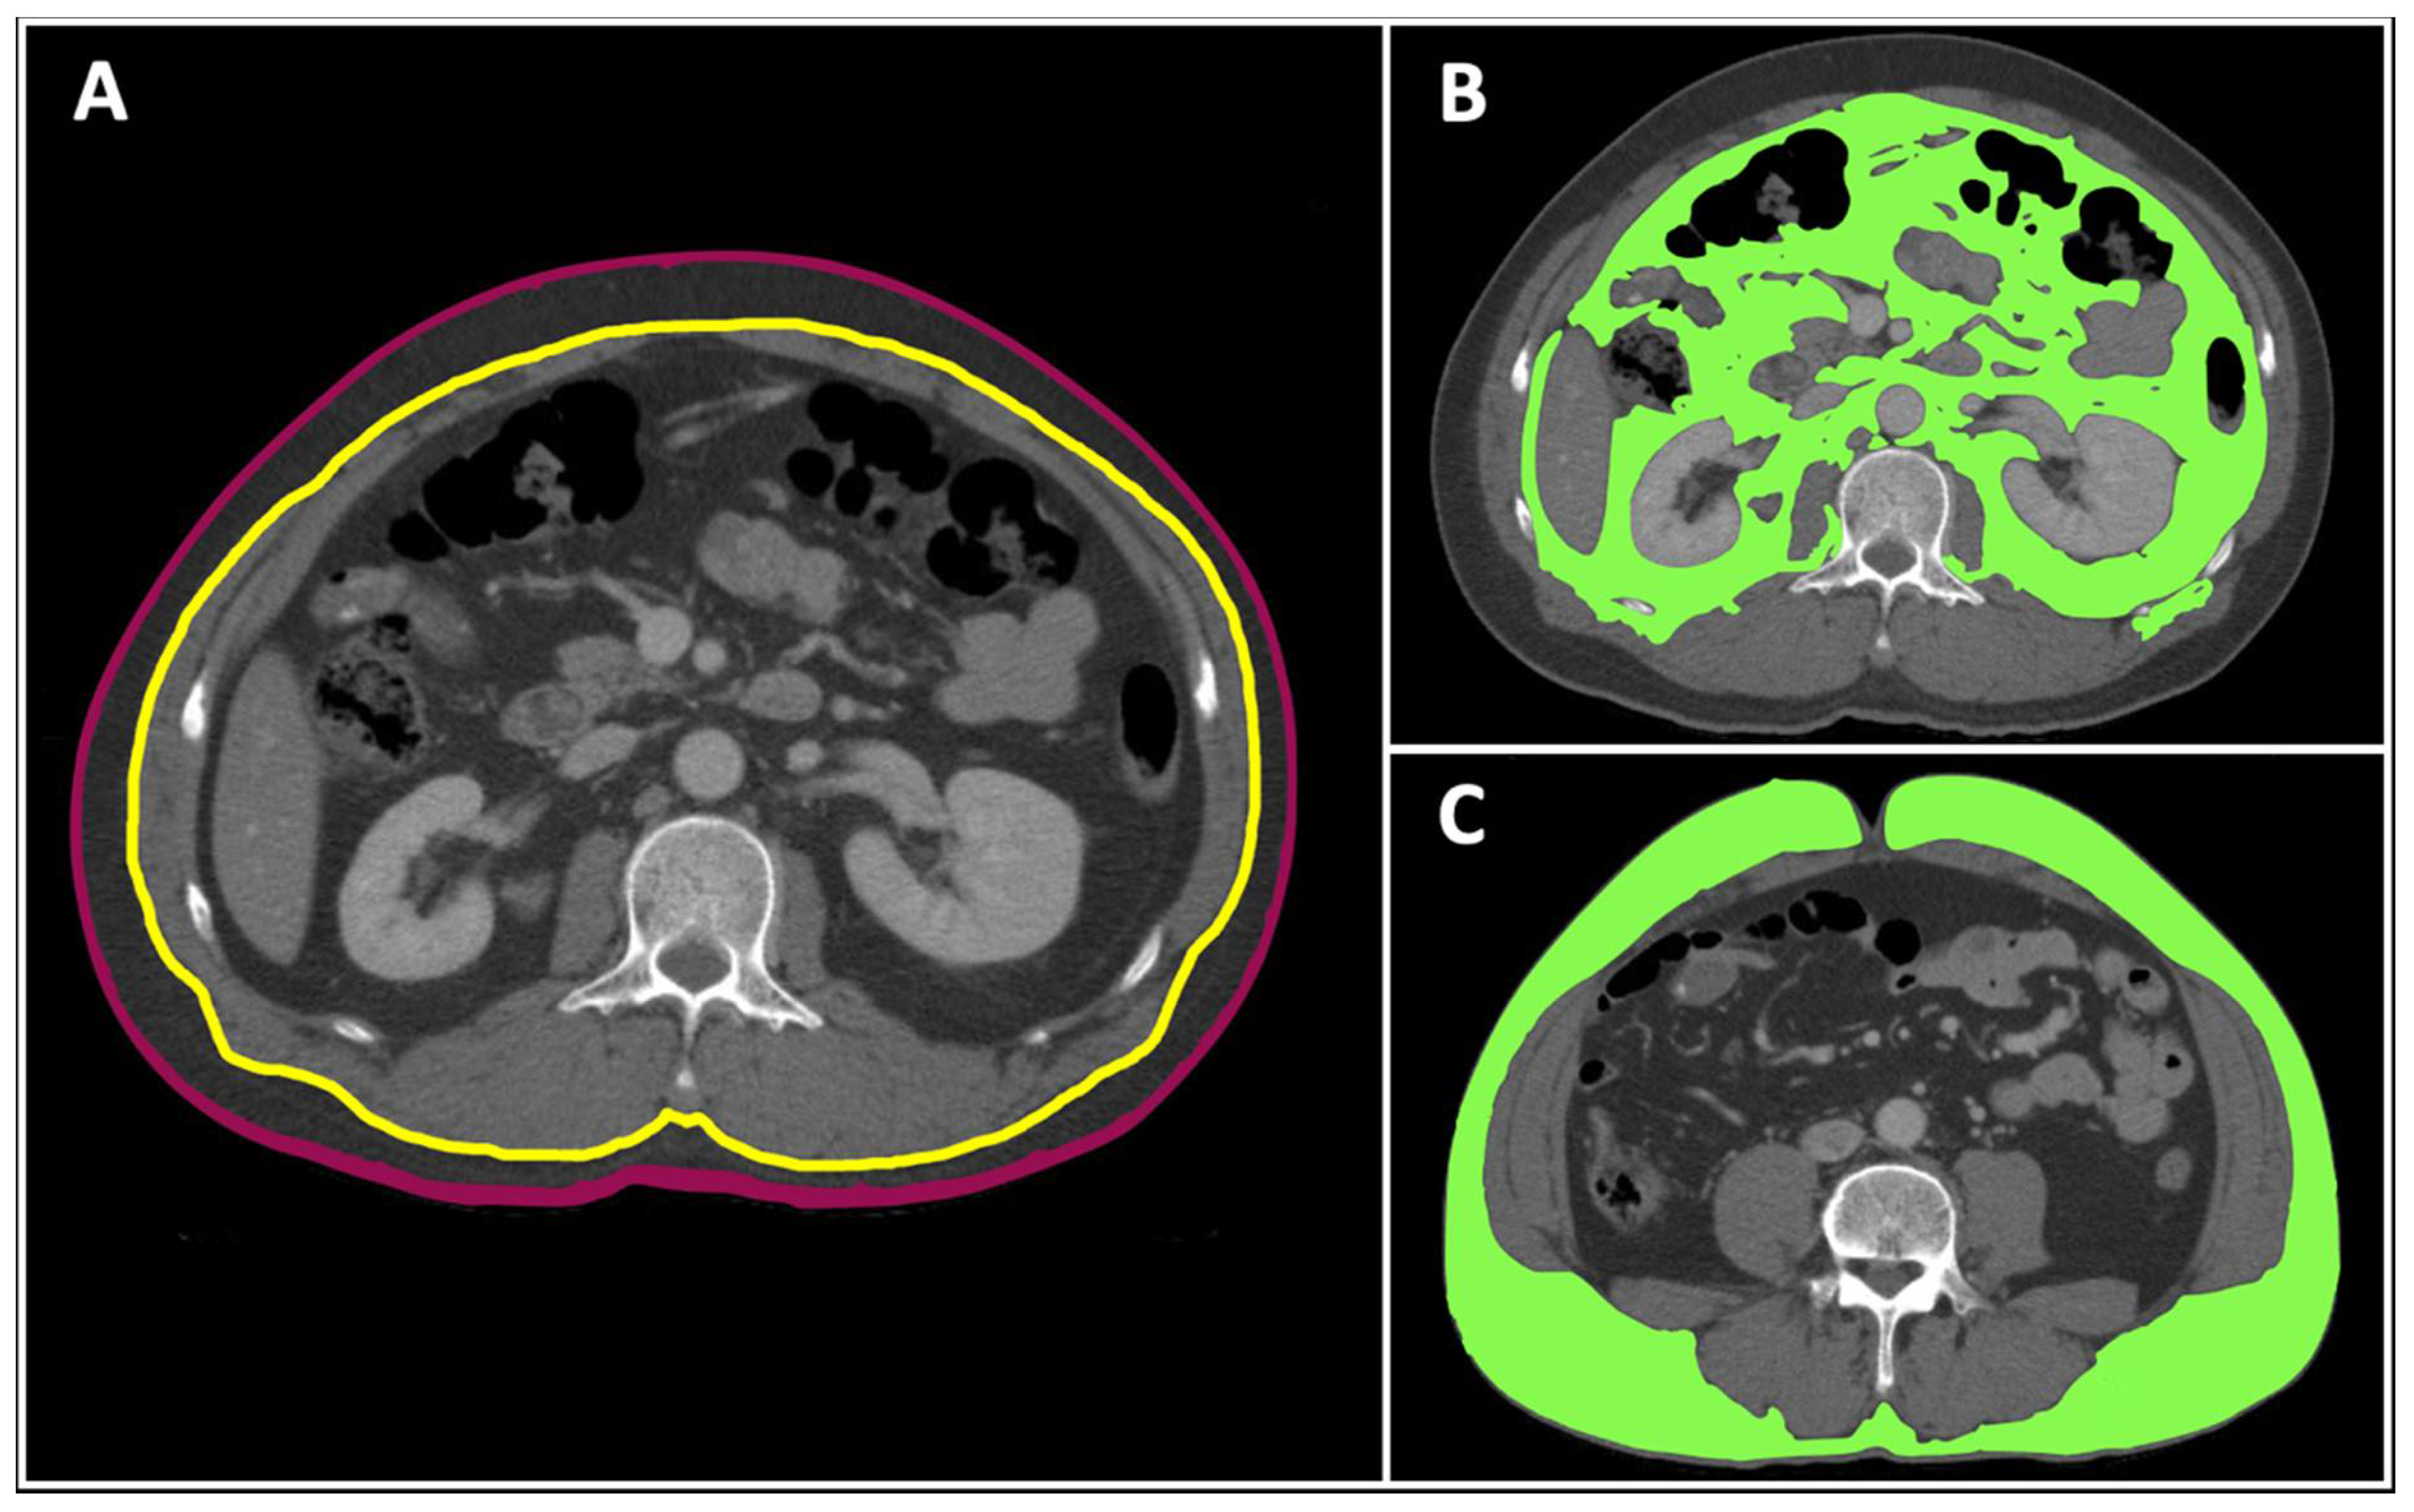

2.2. Morphomic Variables

- TBA: the cross-sectional area of the body.

- Visceral fat area: the cross-sectional area within the fascia with fat density thresholds between −205 and −51 Hounsfield units (HU).

- Subcutaneous fat area: the cross-sectional area between skin and fascia with fat density thresholds between −205 and −51 HU.

- Visceral fat ratio (%) = × 100%.

- SubQ fat ratio (%) = × 100%.